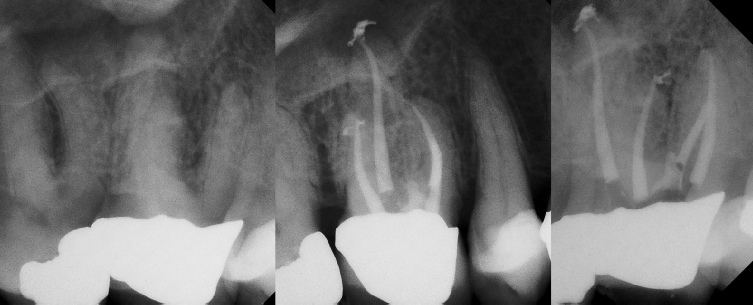

COMPLICATED ANATOMY LARGE LESIONS CALCIFIED CANALS PERFORATION / RESORPTION SEPARATED INSTRUMENTS SURGICAL CASES RETREATMENT / pOST REMOVAL OPEN APICES ACCESS THRU CROWNS Root Canal Case Portfolio